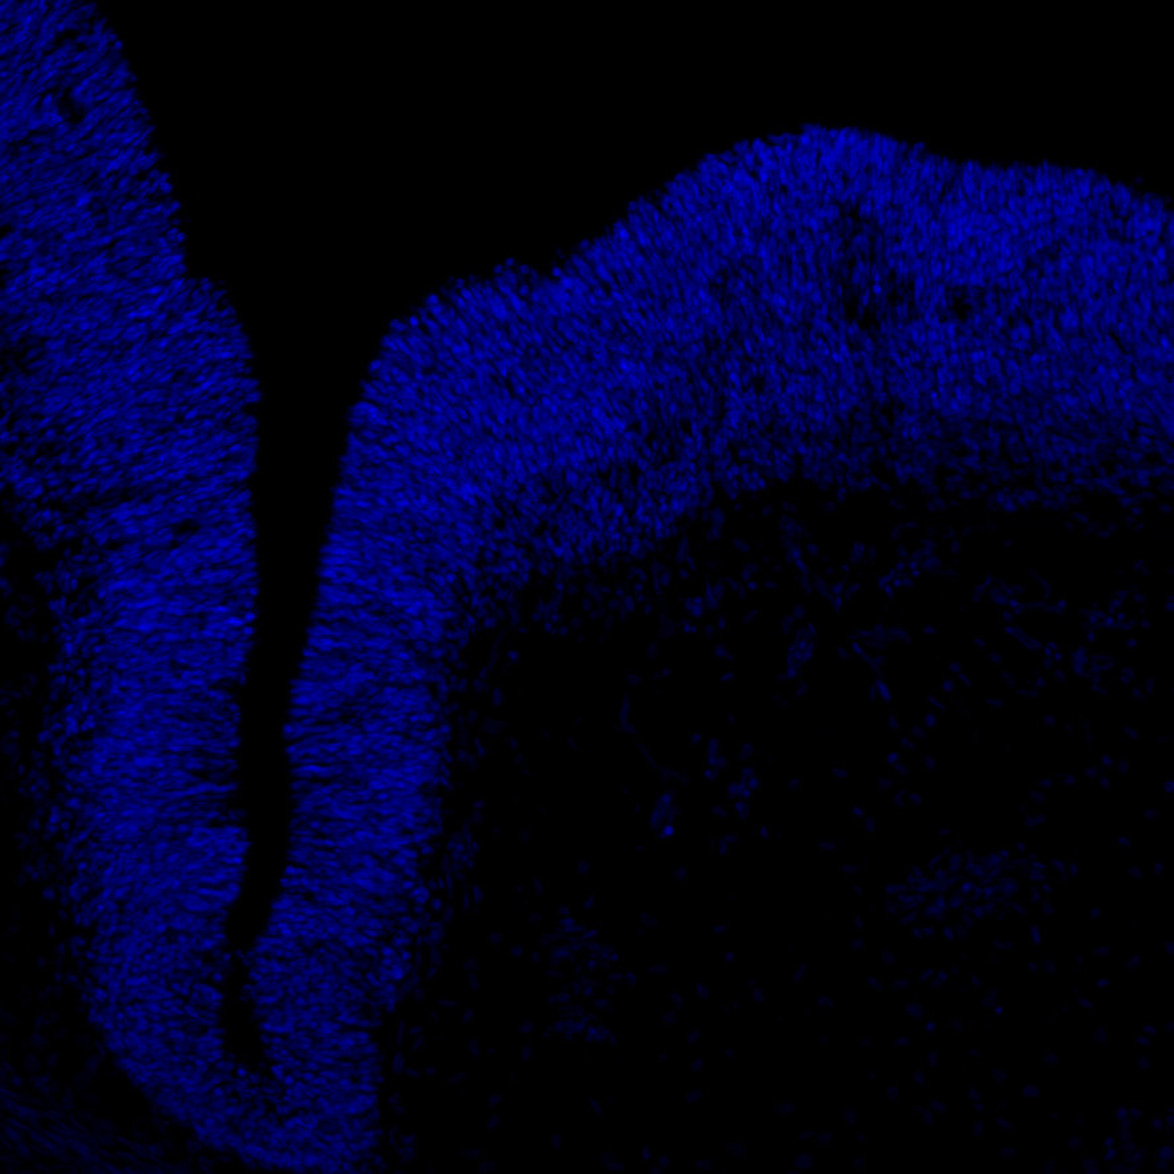

An anatomical analysis of the developing human midbrain from 6 post-conceptional weeks (PCW) to 22 PCW reveals increased tissue complexity, characterized by the emergence of dopaminergic nuclei, as highlighted by immunofluorescence analysis for tyrosine hydroxylase (TH).

DAPI

7PCW human midbrain

MAP2